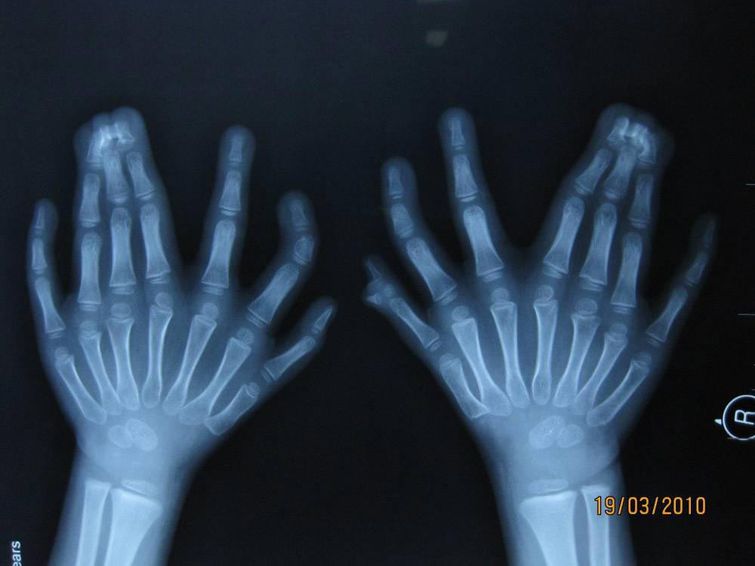

Рентгеновские снимки 6-летнего мальчика, сделанные в больнице Шэн Цзин, Китай

Этот мальчик установил рекорд по количеству пальцев, которых на его руках и ногах насчитывается ровно 31